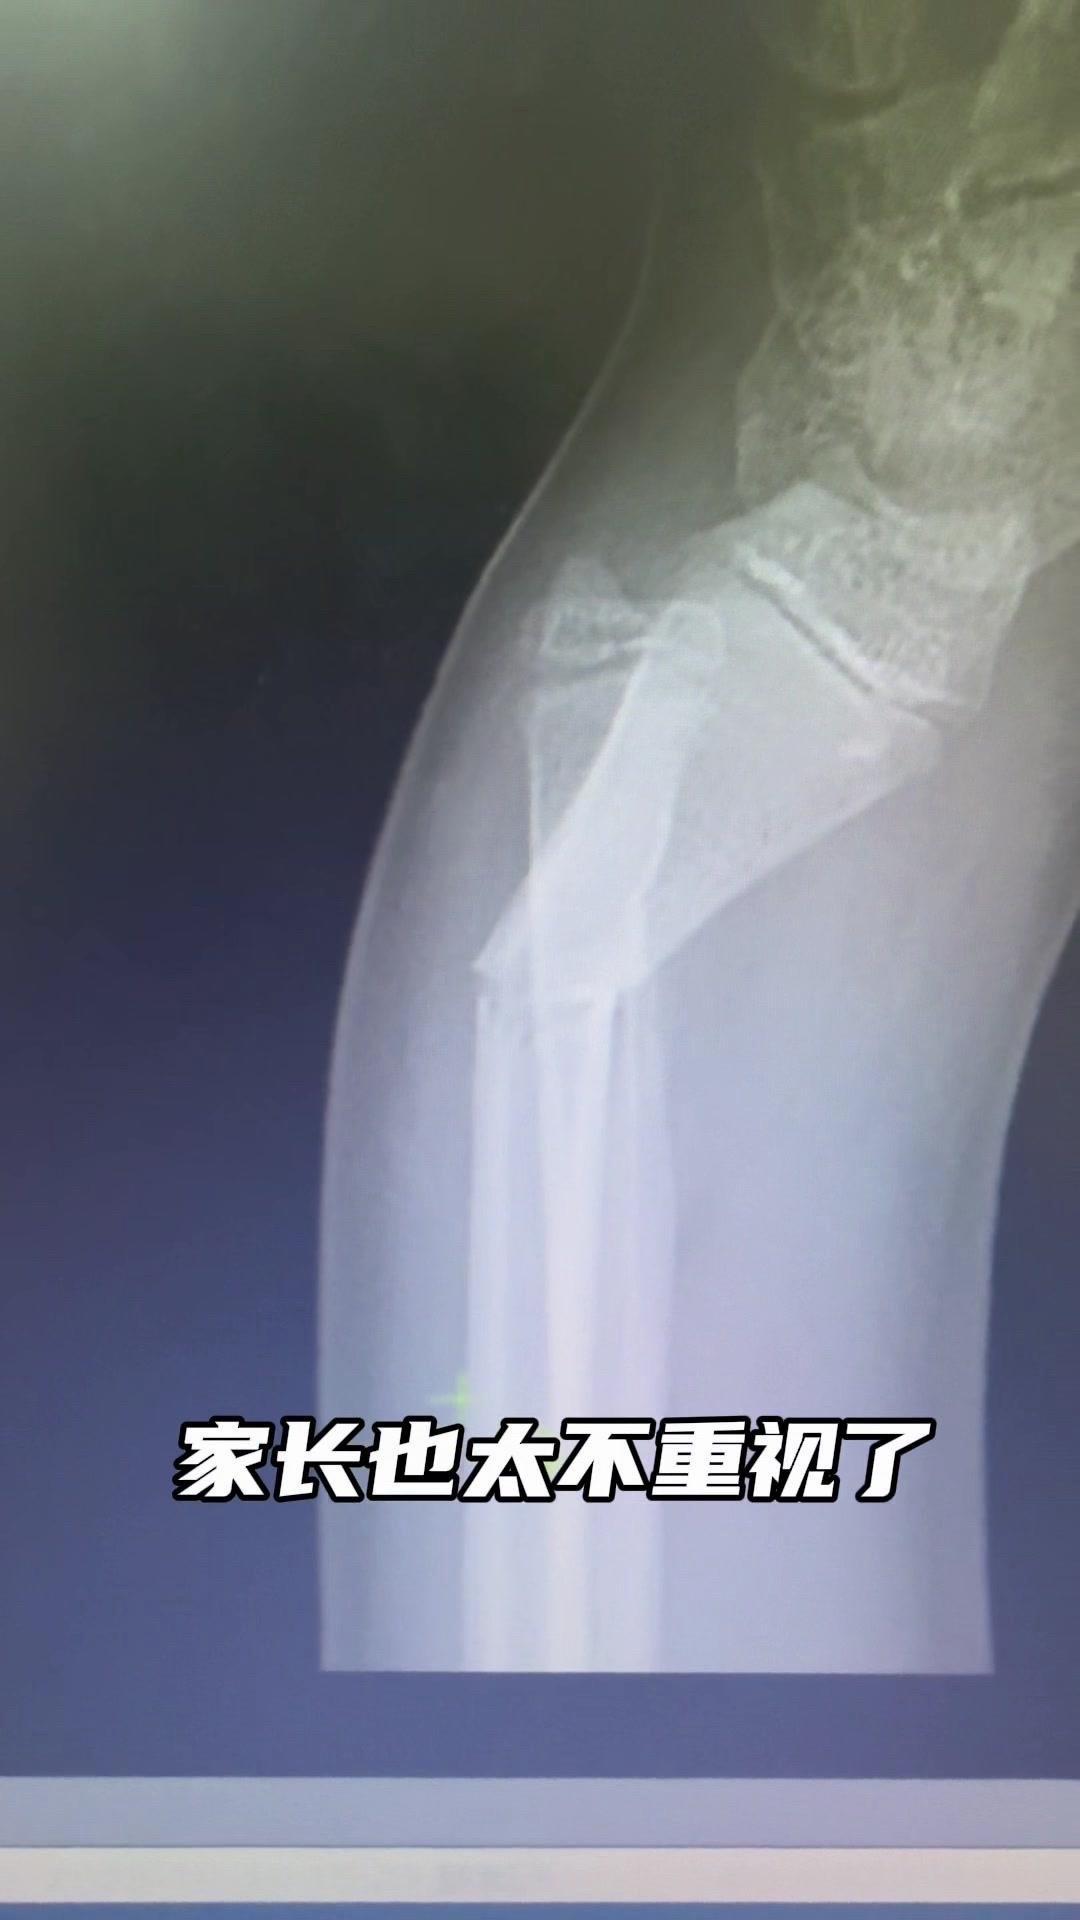

儿童骨折别拖延!💡上周接诊一个10岁女孩,摔了一跤后腕部疼痛还伴有畸形,家长觉得是小伤没在意,结果一周后孩子疼得更厉害,畸形也更明显了。来医院拍片一看,妥妥的骨折,而且才一周就开始出现模糊骨痂,掌区还有45度左右的成角畸形。家长这才意识到问题严重性,其实孩子受伤后出现疼痛、畸形,哪怕看起来不严重,也得及时检查,别让小问题拖成大麻烦。